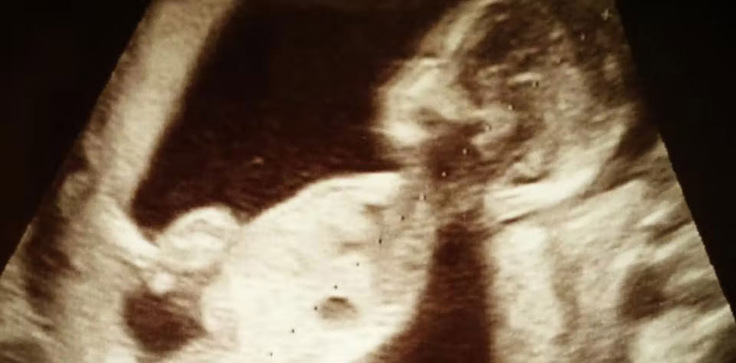

2013年7月

超音波エコーで娘の重度の心臓病が発覚。

出産前からはじまった片道100kmの通院